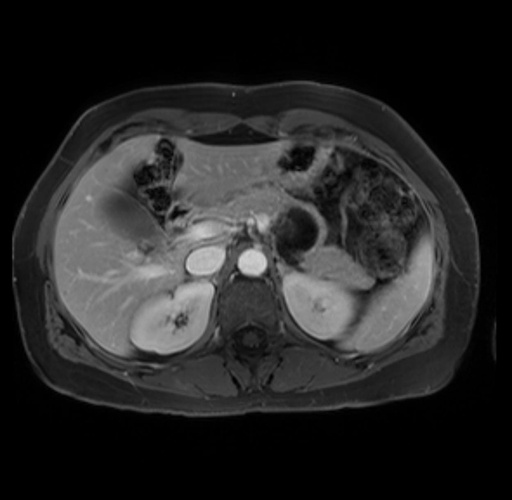

Imaging Analysis

Look through the patient's CT scan to identify any areas of concern for the necessary procedure.

Based on your CT findings, which issue(s) are present and would give reason for "planned slowing down moment(s)" in this case?

Considering a standard distal pancreatectomy procedure, what step(s) of the operation would you do differently in this case?